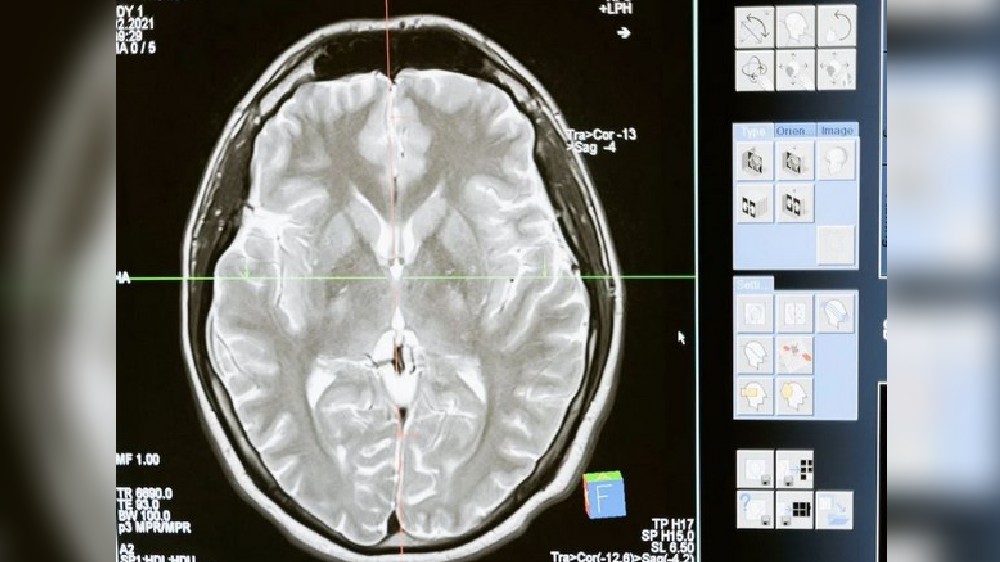

Huntington's disease -- a progressive and inherited brain disorder that causes nerve cells in the brain to break down

Study reveals how Huntington's disease affects different neurons

21 Jan 2023 8:59 AM ISTNeuroscientists at MIT have now shown that two distinct cell populations in the striatum are affected differently by Huntington's disease.